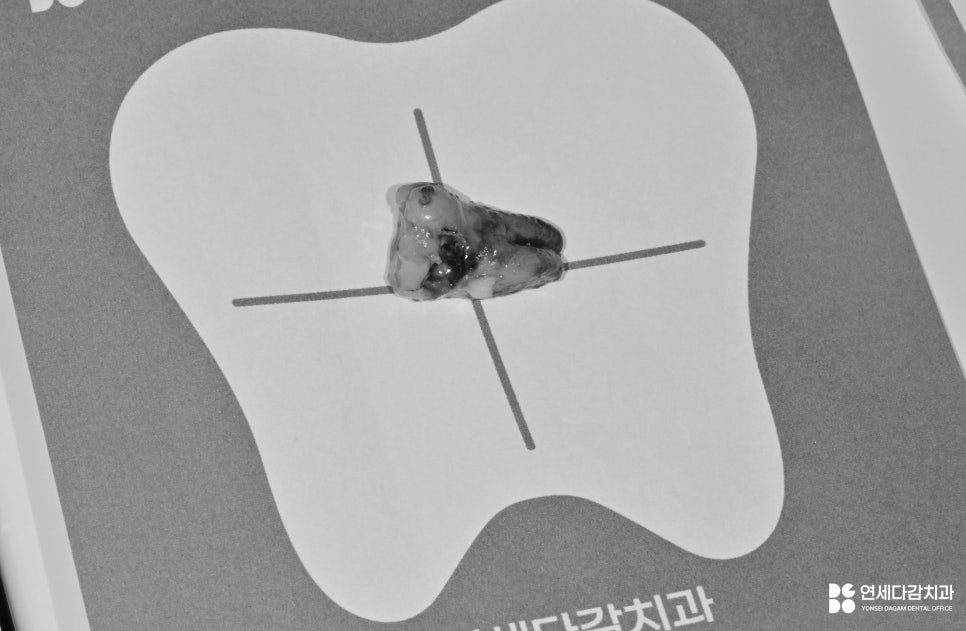

이미 뿌리가 약해진 상태에서는

장기적인 유지를 기대하기 어렵고

결국 발치로 마무리되는 경우가 많습니다.

기능 회복을 위해 임플란트를 심은 모습입니다.